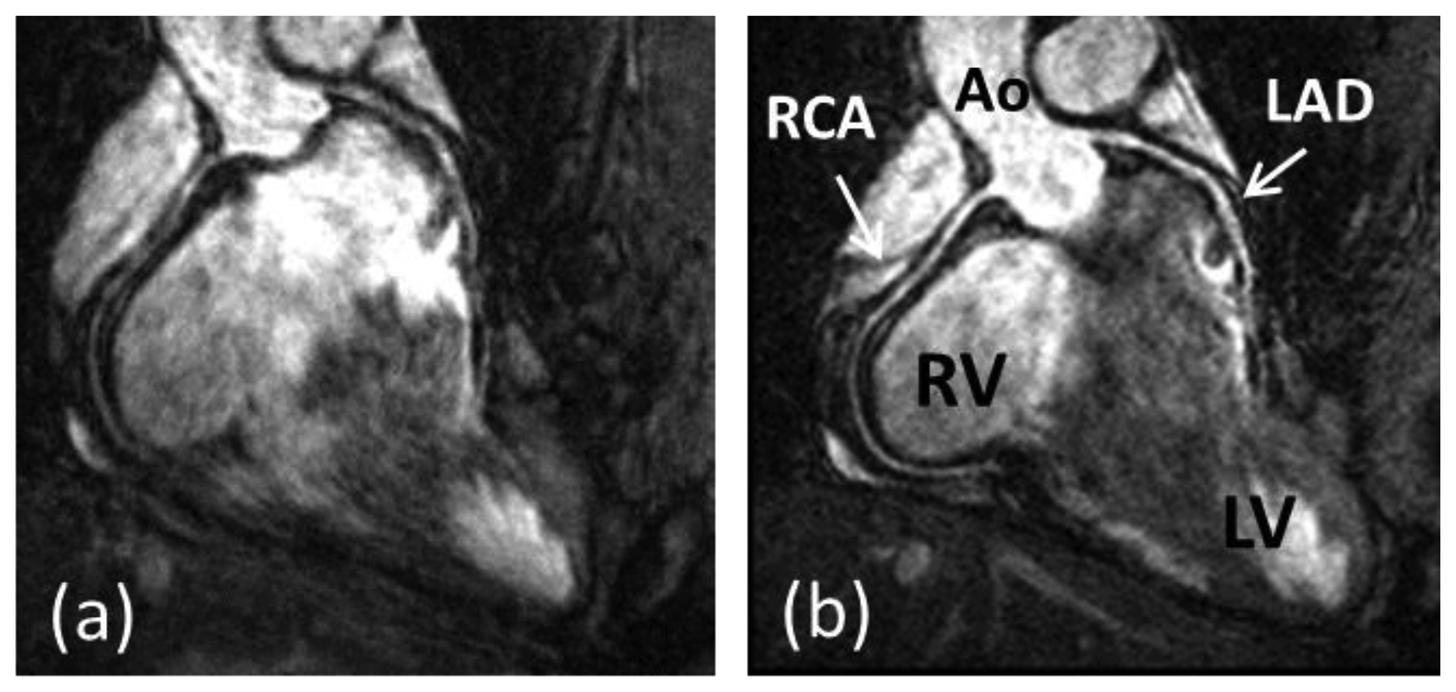

Coronary artery disease (CAD) is the leading cause of death in the Western world and developing countries [1]. The gold standard imaging modality for detection of CAD is X-ray angiography, which is invasive, exposes patients to potentially harmful radiation and requires iodinated contrast agents. Multi-Detector Computed Tomography (MDCT) has been shown to be a reliable technique for non-invasive detection of coronary artery stenosis [2]. However, MDCT, like X-ray, utilizes ionizing radiation. Furthermore, the diagnostic accuracy of MDCT is reduced in patients with heavily calcified plaques. In recent decades coronary magnetic resonance angiography (CMRA) has emerged as a non-invasive alternative for the diagnosis of CAD without exposing patients to potentially harmful radiation or nephrotoxic contrast agents. But despite advancements in CMRA hardware and software techniques, artifacts due to residual coronary artery motion remain an impediment to diagnostic CMRA in a small but significant amount of patients. Several studies have investigated respiration induced coronary motion along the foot–head (FH), left–right (LR), and anterior–posterior (AP) directions throughout the respiratory cycle [36]. Although the principal motion component is predominately in the FH direction and is often one order of magnitude larger than the CMRA spatial resolution, the displacement magnitude in the LR or AP direction has high subject specific variability and can contribute to motion artifacts in CMRA. Furthermore, rotation and non-rigid motion such as affine or even non-linear deformation may occur between the end-expiratory and end-inspiratory respiratory phase [710]. As a result, CMRA is particularly susceptible to respiratory motion artifacts due to the relatively slow data acquisition speed of MRI and the high spatial resolution required to visualize the coronary artery lumen. The main coronary arteries, which consist of the right coronary artery (RCA) and the left main (LM) artery which branches into the left anterior descending (LAD) artery and left circumflex (LCX) artery, have a diameter of approximately 3 mm in the proximal coronary segments which reduces to 1 mm in more distal segments. A respiratory motion corrupted CMRA dataset is shown in Figure 1(a), along with the same dataset after respiratory motion correction in Figure 1(b), reformatted to visualize the RCA and LAD.

Figure 1. CMRA dataset without respiratory motion correction (a) and with respiratory motion correction (b). The 3D dataset is reformatted to visualize the right coronary artery (RCA) and left anterior descending artery (LAD). Ao = ascending aorta; RV = right ventricle; LV = left ventricle. Adapted from [11].